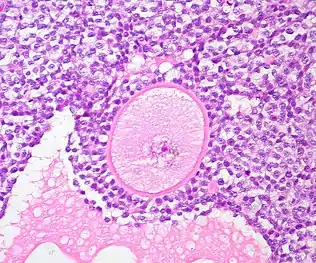

Graafian follicle of the human ovary